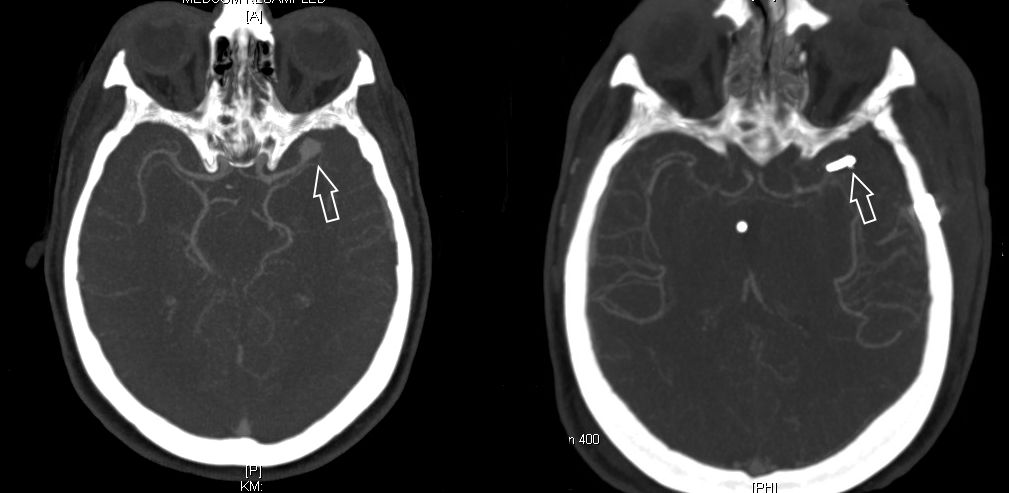

CT-Angiographie eines gebluteten Aneurysmas

Als diagnostische Maßnahme wird in der Regel ein craniales Computertomogramm (CCT) durchgeführt. Intrazerebrale Blutungen lassen sich mit dieser Methode sicher diagnostizieren.

Bild einer intracerebralen Blutung nach OP.

Bild einer intracerebralen Blutung vor OP.